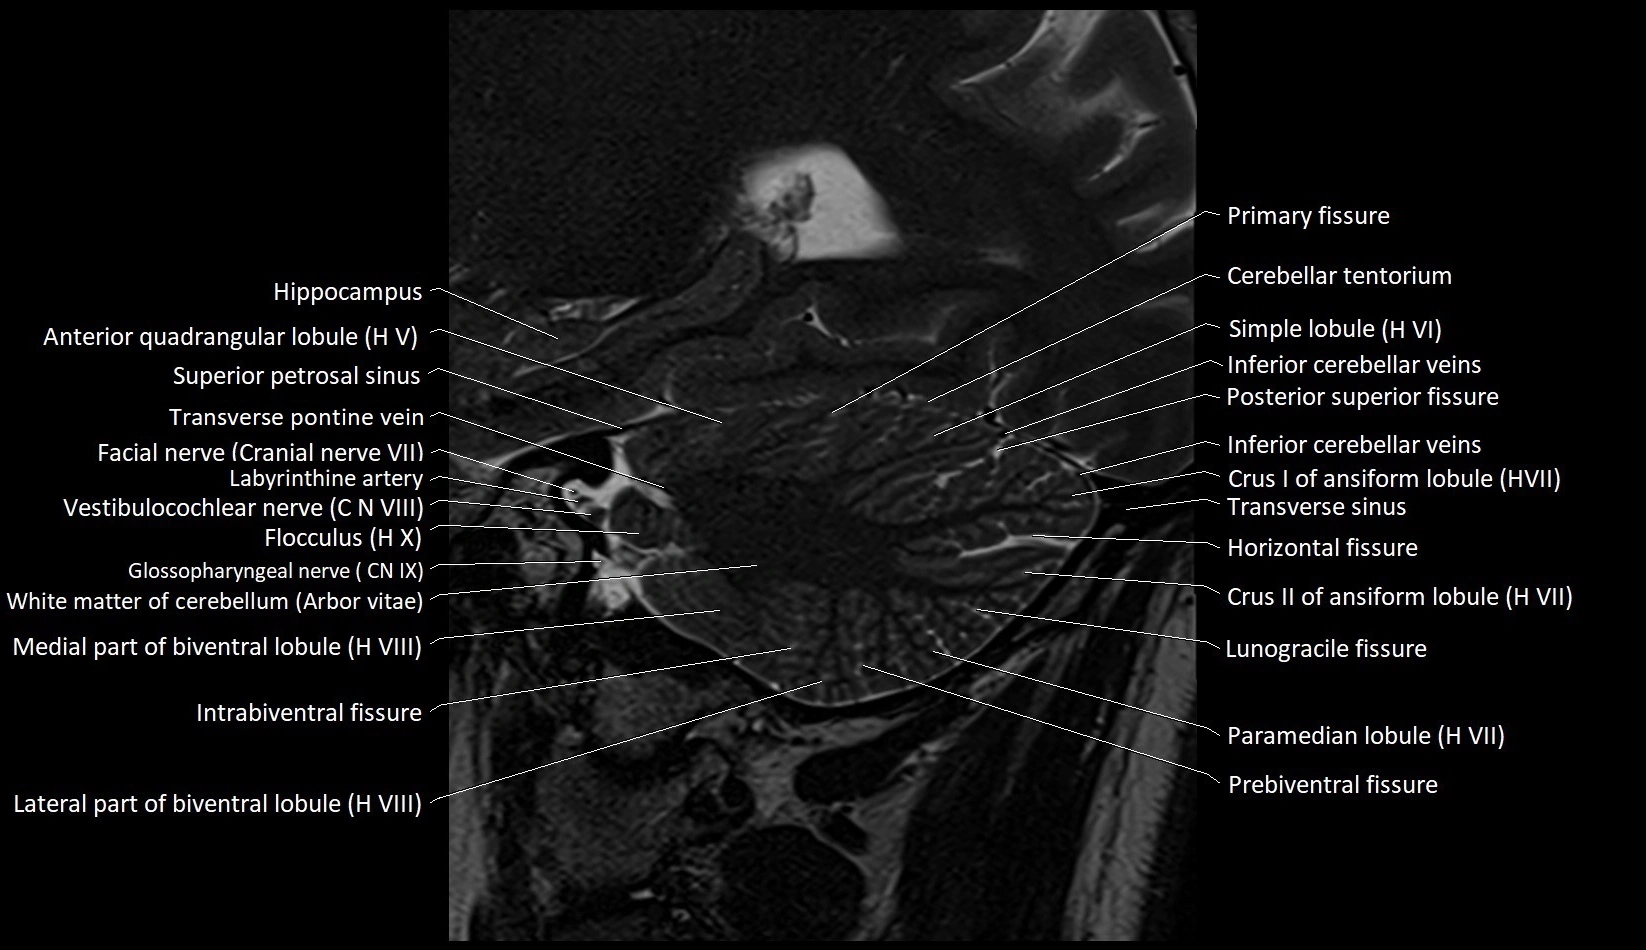

MRI images